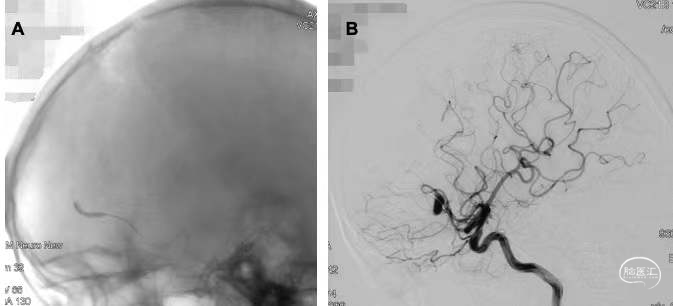

入院后DSA检查见右侧大脑前动脉A3段及大脑中动脉M3段局部梭形膨大(图2)。梭形动脉瘤无法按常规方式夹闭瘤颈,需闭塞载瘤动脉。考虑大脑前动脉动脉瘤位于胼周动脉主干,闭塞可能造成功能障碍,而中动脉动脉瘤位于非功能区,故于手术前先行右侧大脑前动脉球囊闭塞实验。在局麻下,全身肝素化,双侧股动脉穿刺置鞘,将导引导管置入至右侧颈内动脉岩骨段,取球囊1枚超选入右侧大脑前动脉A3段,在动脉瘤近端充盈球囊,造影见球囊远端动脉无显影,提示闭塞良好(图3)。另取一造影管超选至左侧颈内动脉、左侧椎动脉造影,未见明显血流逆向充盈动脉瘤。共闭塞20min,过程中患者无明显不适,对答良好,四肢肌力无下降。

图3. 球囊闭塞实验过程中造影图像 3a为球囊充盈后不剪影图像,示球囊充盈良好;3b为球囊充盈后右侧颈内动脉造影图像,示右侧大脑前动脉远端不显影。